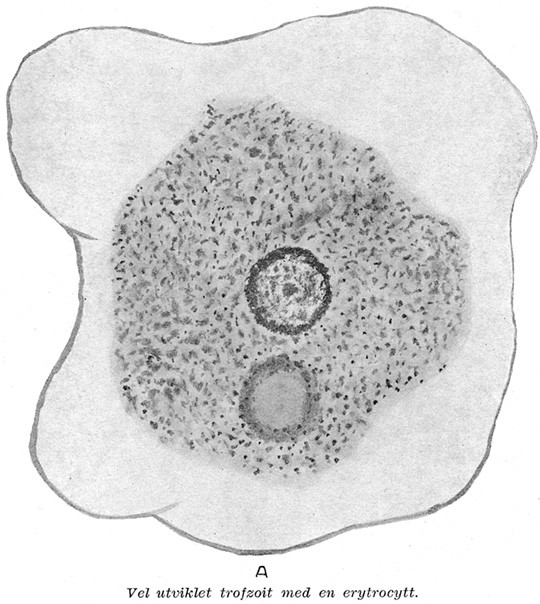

I Tidsskriftet nr. 4/1936 presenterte Mentz Lillo Rynning von Krogh, som hadde vært professor i bakteriologi i Argentina, sitt foredrag om en interessant – ikke sjelden – tilstand. Dysenteri, som betyr «smertefull avføring», hadde «efter den gamle opfatning sitt sete i de varme land». Sykdommen skyldtes en amøbe, det var man allerede «i forrige århundre» kommet på det rene med – og «man synes nu å være blitt enig om å kalle den entamøba histolytica». Men i kaldt klima er symptomene annerledes: «Jo koldere klimaet er, desto mer mister sykdommen sin akutte karakter, optrer ekskvisit kronisk og presenterer symptomer som ikke har nogen som helst likhet med den akutte diarretilstand som vi kjenner som dysenteri.» Matintoleranse, tretthet og nervøse symptomer må skyldes et toksin som amøben produserer, mente von Krogh (Tidsskr Nor Lægeforen 1936; 56: 169 – 78).

Kronisk dysenteri i Norge med spesielt henblikk på våre sjøfolk.

Forelesning holdt på Universitetet 3. oktober 1935.

Av Mentz von Krogh, Oslo.